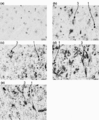

- the drawing substitute photograph which shows the result of the immunohistochemical dyeing

- A No administration of anti-hTfR antibody,

- b administration of anti-hTfR antibody No. 1,

- c administration of anti-hTfR antibody No. 2,

- the bar on the lower right of each photograph is a gauge representing 50 ⁇ m.

- the drawing substitute photograph which shows the result of the immunohistochemical staining for the humanized anti-hTfR antibody of the cerebral cortex of the cynomolgus monkey after single intravenous administration.

- A administer Herceptin,

- b administer humanized anti-hTfR antibody # 3,

- c administer humanized anti-hTfR antibody # 3-2

- d administer humanized anti-hTfR antibody # 3

- E Administration of humanized anti-hTfR antibody No. 3-2 (IgG4).

- the bar on the lower right of each photograph is a gauge representing 20 ⁇ m.